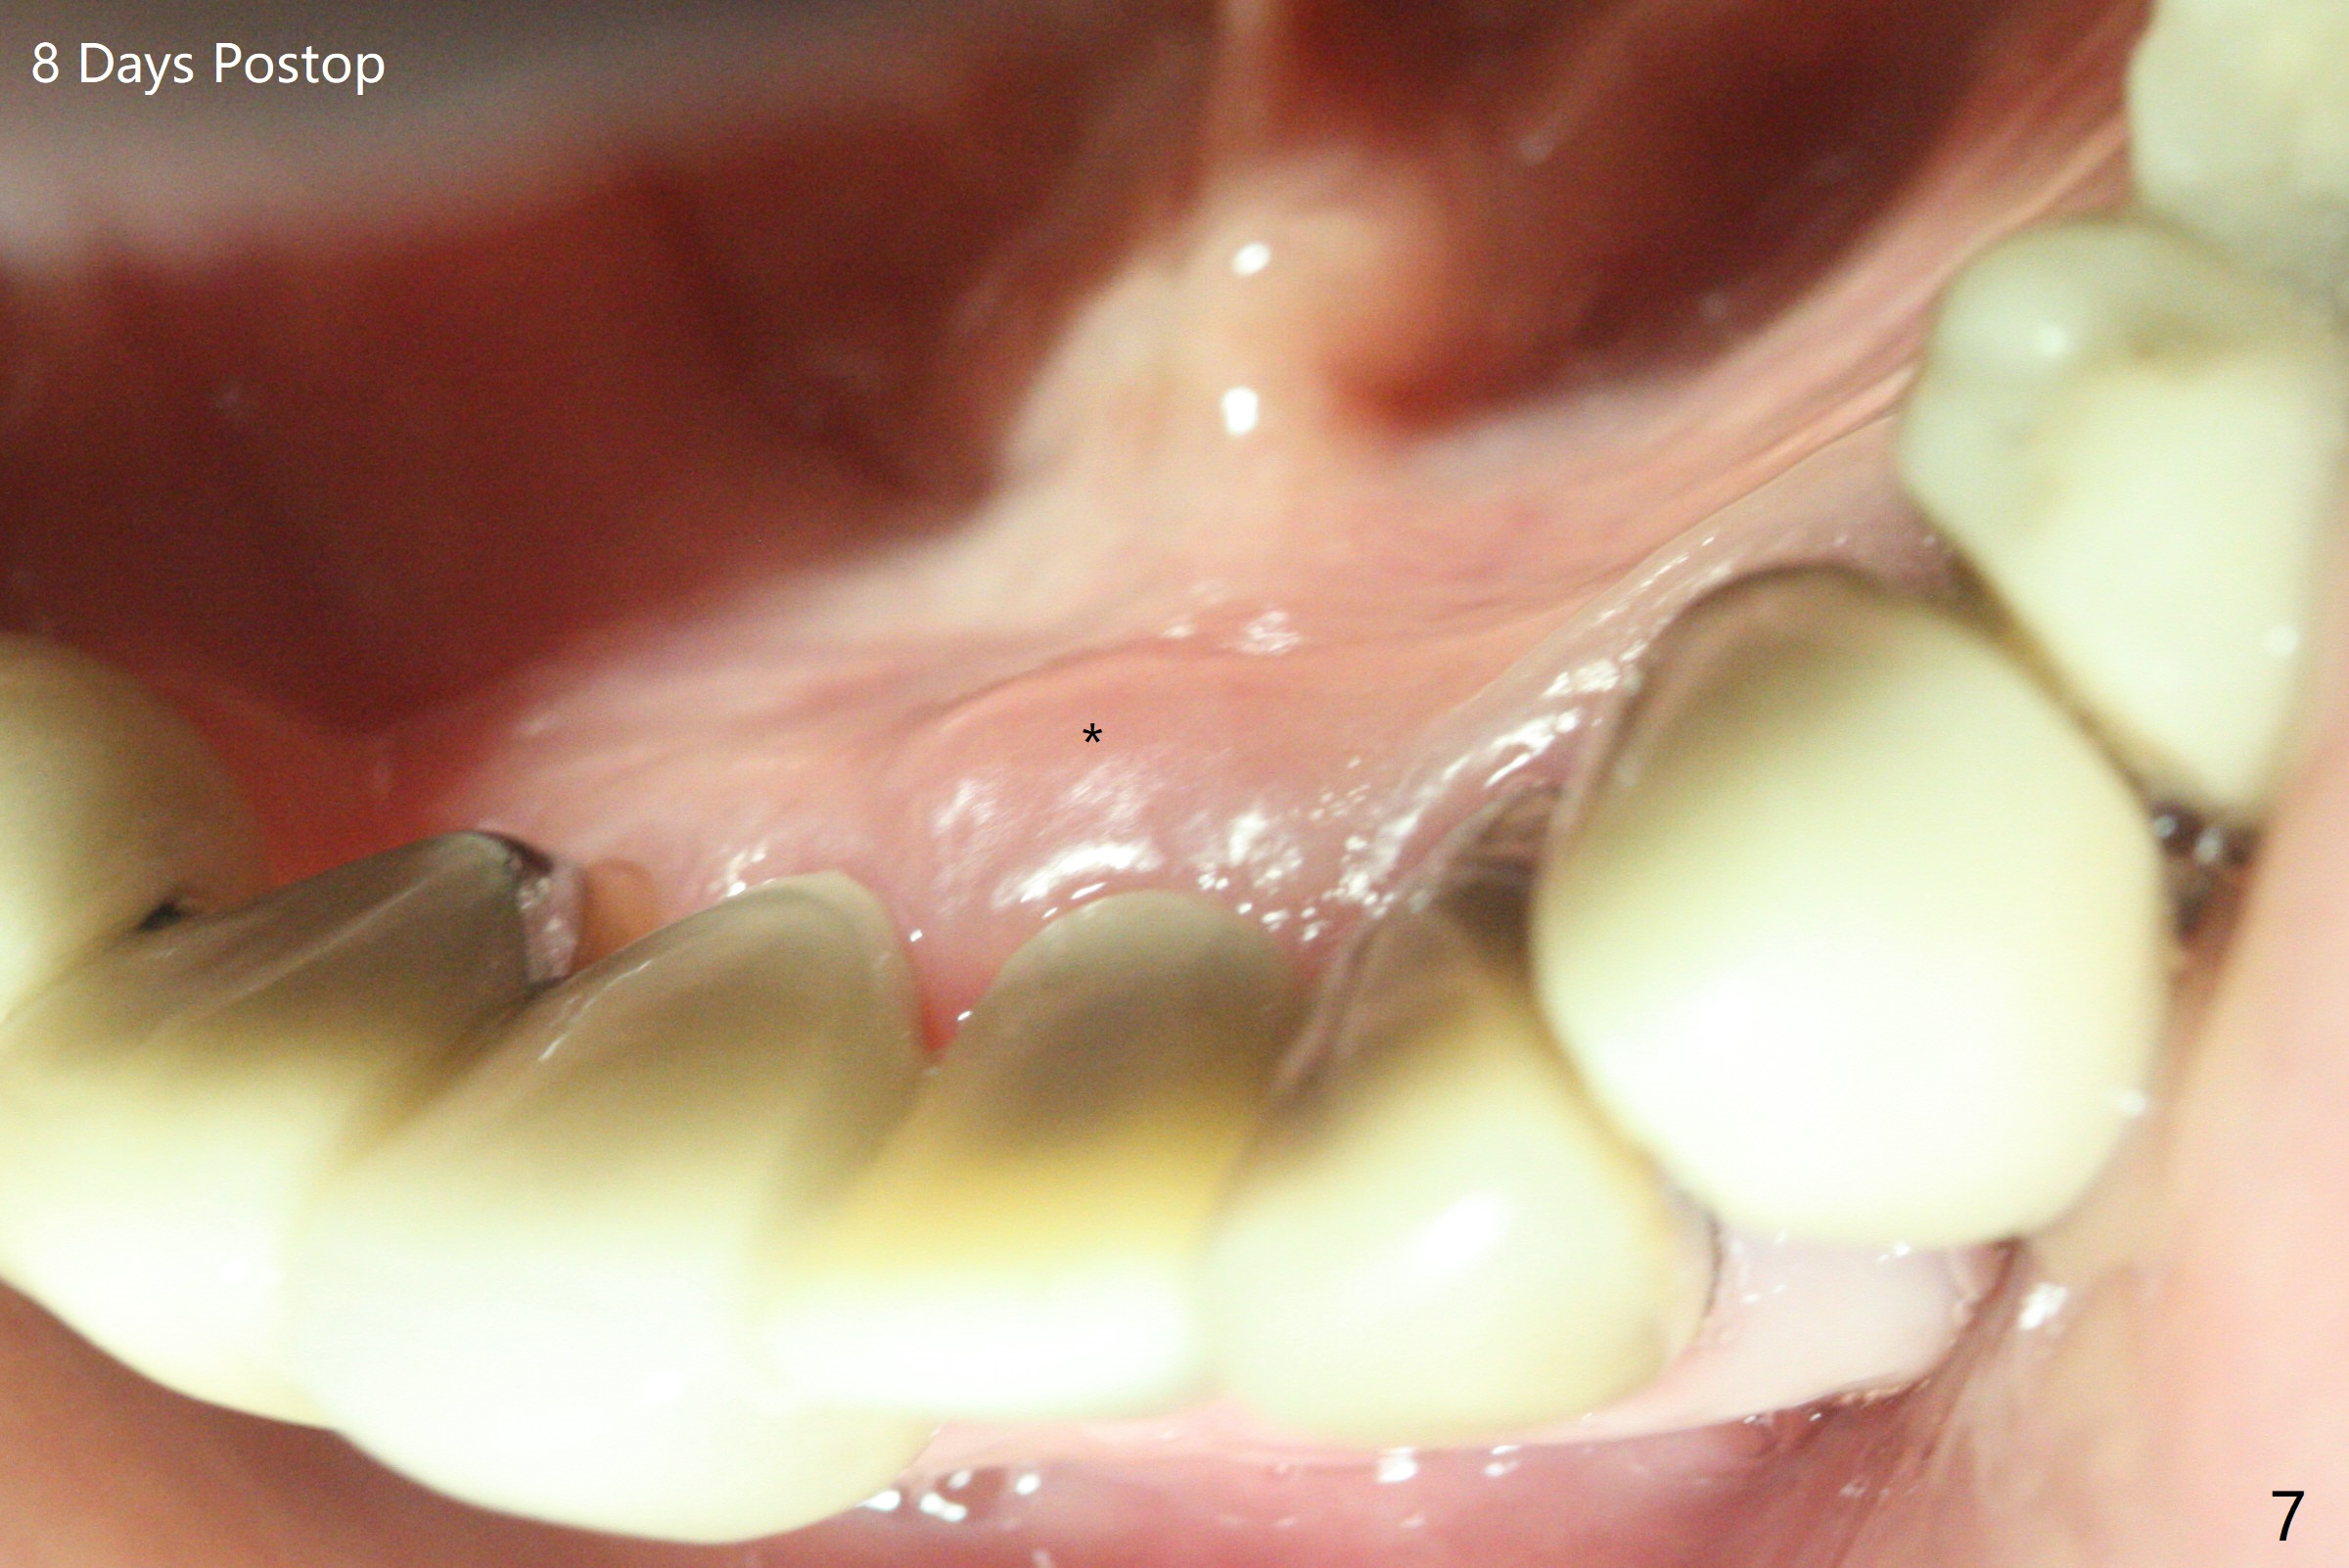

After extraction of the tooth #24 with vertical root fracture (loss of buccolingual plates), osteotomy is initiated with 1.2 mm drill free hand; the trajectory seems satisfactory (Fig.1). With sequential osteotomy, a 2.5x14(2) mm 1-piece implant has difficulty being placed deep (Fig.2), apparently associated with dense bone. Allograft is placed not only mesiodistal (Fig.2,4 *), but also buccolingual (Fig.3,5,6 *) to cover the exposed implant threads. In fact inability to place the implant deep is due to the apex of the implant (Fig.5,6 x) touching the lingual (L) cortical plate. If surgical guide were used, the implant placement difficulty would not occur. The surgery would be shorter and easier. The seemingly easiest implant placement should be assisted with a guide! In addition, preop CT would dictate implant placement in the middle of the socket buccolingual. The lingual (Fig.7 *) and buccal (Fig.8 <) gingiva remains bulky, although asymptomatic, 8 days postop.